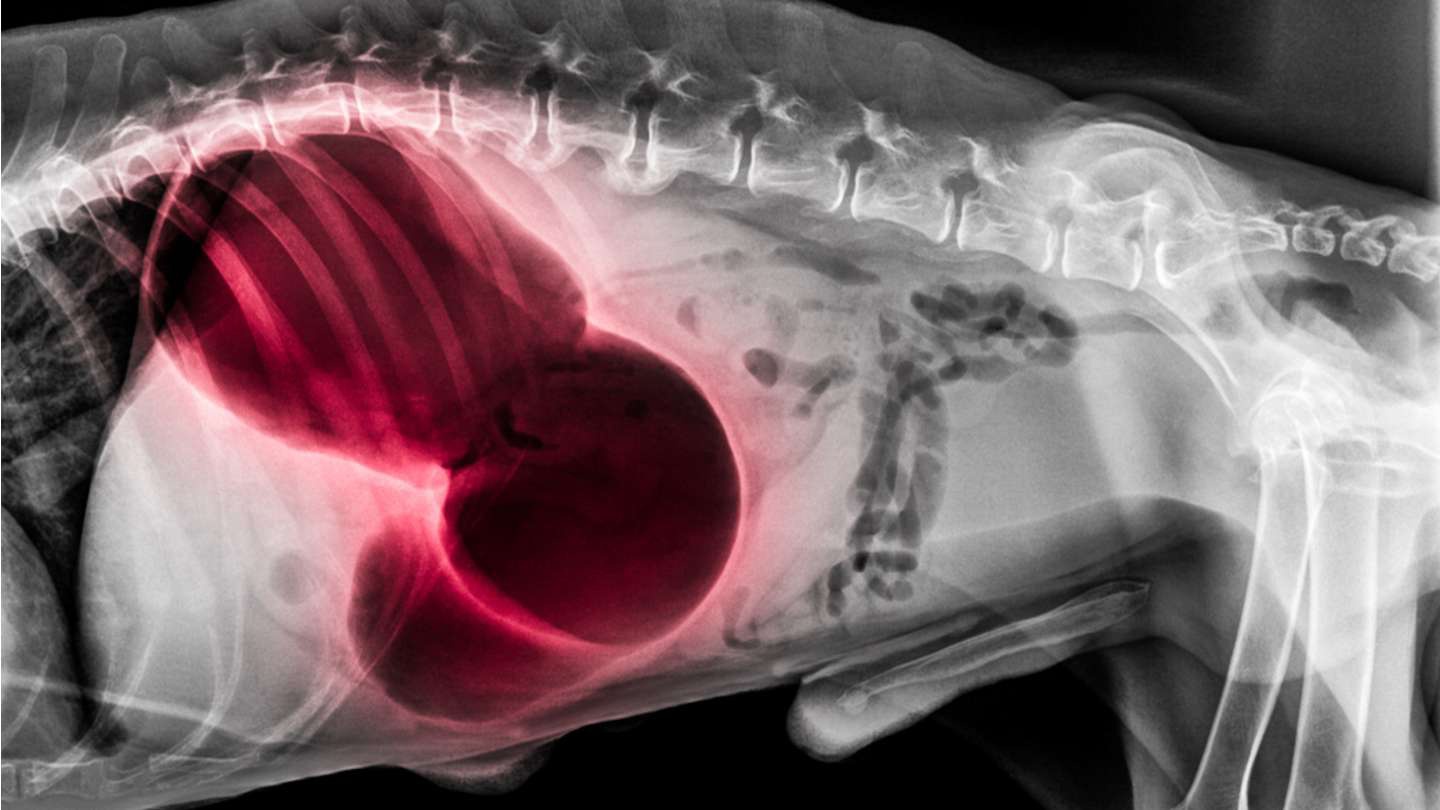

También llamada torsión de estómago, es una patología en la que el estómago de nuestro compañero se gira alrededor de su propio eje, generalmente media o una vuelta. Además de la rotación que modifica la posición anatómica normal, el perro también sufre una distensión que no es habitual. En consecuencia, la boca superior e inferior del estómago se ve comprimida, lo que impide el paso de alimentos, pero también de líquidos y gases. Sumado a ello, la dilatación del estómago también comprime órganos abdominales y torácicos, así como vasos, afectando el funcionamiento de los mismos. Esto último, favorece que el perro entre en estado de shock debido a la falta de circulación sanguínea que va desde el abdomen hasta el corazón. Otras complicaciones que pueden aparecer son la necrosis de la pared intestinal y la pared gástrica con perforación (peritonitis), arritmias, insuficiencia renal e insuficiencia hepática.